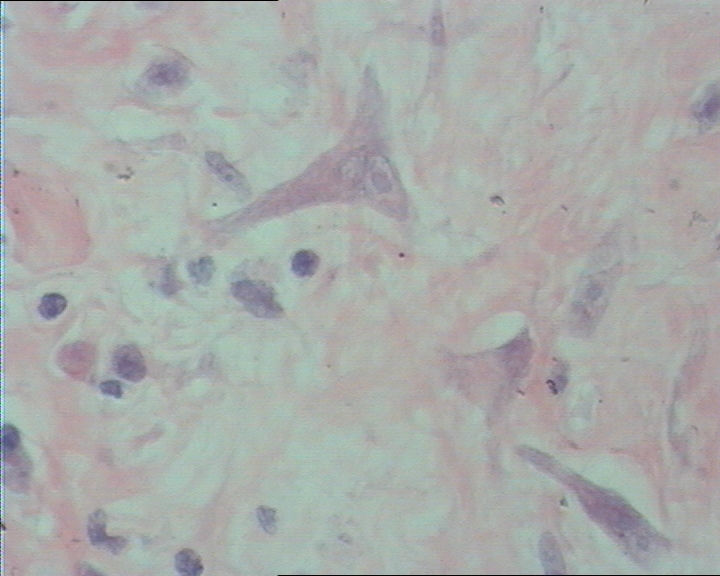

右肘部肿物

图2

右肘部肿物,无包膜,3.8cm*3.0cm*2cm,切面灰白淡黄相间。